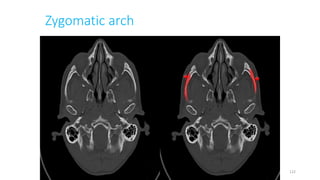

Zygomatic arch

122